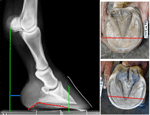

Fig 1. The radiograph shows a hoof that has a good stance. The arch (red curve) supports the larger part of the pedal bone. The vertical green line intersecting the pedal bone is placed approximately where the apex of the frog would be. As one can see, a large portion of the hoof lays behind this line. The two solar pictures of the hoof show two different hooves with reasonably good conformation. Note that a larger portion of the hoof is behind the red line in the two solar views

My ballpark definition of a ‘normal’ hoof is this: the hoof ought to stand under the bony column and have heels that provide adequate support to the bulbs (Fig 1). A higher percentage of the hoof should be behind the apex of the frog, than in front of it. It makes sense to have a larger load percentage present in this area rather than at the toe. The caudal area of the hoof (approximately, the region that lies behind the middle part of the frog toward the bulbs) can be regarded as functioning as a pad. Shifting the load to the toe area has serious consequences on the health of the pedal bone. Internally, the arches should have a good definition. The sole should be at least half an inch in thickness or more. The sole plays an important part in supporting the entire limb. It acts as a shock absorber and provides insulation against the cold and heat. If possible, the hoof should not present internal pathologies, that is, articular ringbone, nor external abnormalities, such as permanent scars on the hoof capsule. Ideally, the hoof should be able to function as intended. This means that the sole, walls and frog should share the load and be able to flex according to their normal mechanical properties.